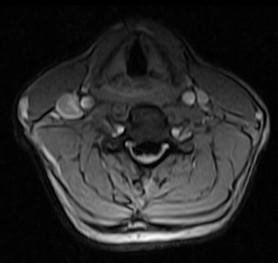

October 2005 - Ossification of the Posterior Longitudinal Ligament (OPLL)

There is evidence of a markedly thickened/ossified posterior longitudinal ligament over the C3 to the C7 vertebral levels with resultant canal stenosis and cord compression. The cord shows a hyperintense signal on the T2W images and is also decreased in caliber (edema/ischemia/gliosis - myelomalacia).

OPLL may be classified into different morphological types on the axial CT or MR images.

• Square

• Mushroom

• Hill

Continuous type is usually thicker, may contain bone marrow and is most frequently associated with severe cord compression. Detection is dependent upon the morphology of the process, presence or absence of bone marrow or calcium in the ligament or by it's effect upon the ventral subarachnoid space, dura and spinal cord. Hyperintense signal on the T1W images may represent fatty marrow. The hypertrophied ligament is hypointense. Intense enhancement within the ligament may be seen. T2W images help to assess the cord (myelopathy - due to direct compression on the spinal cord and anterior spinal artery).